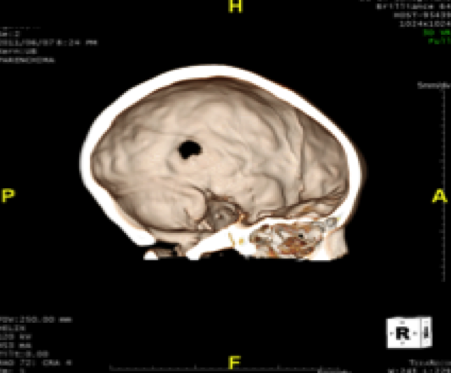

A. � un bambino di 7 anni che giunge in PS per la comparsa di una tumefazione molle in sede parietale sinistra associata a intenso dolore locale ed irritabilit� da alcuni giorni. In anamnesi trauma cranico 15 giorni prima senza sintomi associati. A. � in buone condizioni generali e l'obiettivit�, compresa quella neurologica, � nella norma. Anche gli esami ematici risultano nella norma. Vista la clinica e la storia di trauma cranico, eseguiamo TC cranio che mostra: �in sede extra-assiale parietale sinistra, apprezzabile sottile aspetto tenuemente iperdenso di larghezza 17 mm e spessore 5 mm; in corrispondenza, area tondeggiante di osteolisi di 10 x 10 mm a margini netti, con tumefazione delle parti molli extracraniche�. Per approfondimento diagnostico, eseguiamo RMN cerebrale che evidenzia: �formazione a densit� intermedia di diametro 4 x 2,5 cm in sede parietale sinistra che si localizza su entrambi i versanti del tavolato cranico, a ridosso dell'area di osteolisi.� In considerazione del reperto neuroradiologico, dopo consulenza Oncologica e Neurochirurgica, viene posto sospetto diagnostico di granuloma eosinofilo. Eseguite Rx torace ed eco addome che hanno escluso un possibile coinvolgimento viscerale. A. � stato quindi sottoposto ad intervento di curettage chirurgico che ha dato conferma istologica della diagnosi.